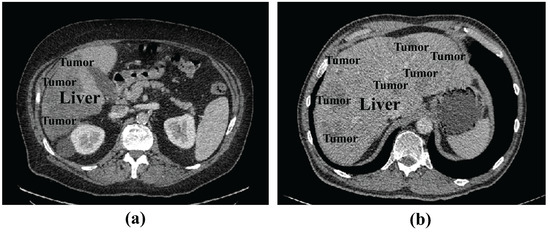

Analysis of the Res-Inception-SE module: To verify the effectiveness of the Res-Inception-SE module, We conducted experiments on the LiTS17 dataset by replacing the convolutional sequences in the proposed RIS-UNet model with Inception V1, Inception V2, Inception V3, and Inception V4, respectively. To ensure fairness, all the experimental settings are the same except that the convolutional sequences are different. The quantitative results are shown in Table 6. Table 6 shows that the model performance gradually improves with the upgrade of the Inception structure. Specifically, RIS-UNet achieves the best performance in all five metrics compared to other models.

Figure 5 shows the visualization results of the experiment, which is a comparison experiment between our model and replacing the convolutional sequences with a different version of the Inception module. We selected three representative tumors for visualization and comparison: tumors located at the liver boundary, multiple tumors with different shape and location, and small tumors.

From Figure 5, we can see the following: (1) When dealing with the tumor located at the liver boundary in Case 1, the models all show some under-segmentation/over-segmentation errors, and the segmentation results of our model (+Res-Inception-SE) as well as the model with Inception-v4 added are closer to the real boundary of the tumor. (2) The tumor locations in Case 2 are varied in size, and in addition to the large tumor in the upper right, Case 2 contains multiple tiny tumors. It can be seen that U-Net successfully segments some tiny tumors but fails to successfully identify the the large tumor in the upper right. In contrast, our model (+Res-Inception-SE) comprehensively identifies and segments all the tumors in the liver. (3) When dealing with small tumors, other models produced additional or missed small tumors, and even some models did not identify the small tumors. In contrast, our proposed method (+Res-Inception-SE) segmented the small tumor region with high accuracy. Overall, our model has more accurate boundary segmentation for large tumors and can also handle small tumors with diverse shapes and locations.